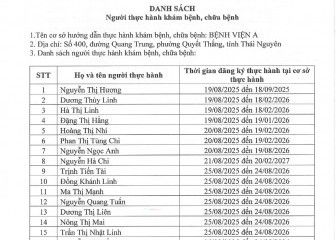

Danh sách người thực hành khám bệnh, chữa bệnh